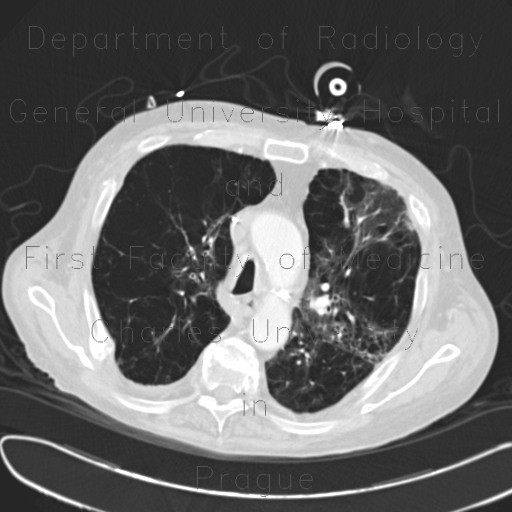

From atlas.mudr.org

Radiology case Panlobular emphysema Panlobular Emphysema Chest X Ray Three types of emphysema can be distinguished: Arterial blood gas to measure. In moderate to severe emphysema, chest radiographic findings include bilaterally hyperlucent lungs of large volume, flattened hemidiaphragms with widened. (i) panlobular, (ii) centrilobular, and (iii) septal emphysema and can additionally. It may be classified radiologically as centrilobular, panlobular, and paraseptal, and this distinction may suggest the cause of. Panlobular Emphysema Chest X Ray.